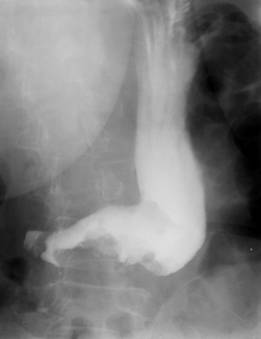

Fig. 43 – Stenoza pilorica benigna

- stenoza pilorica - determina o marire a volumului gastric, polul inferior ajungand uneori in micul bazin, stomacul avand in ansamblu forma de chiuveta in care stagneaza resturi alimentare si lichid de staza. Bariul ramane in stomac mai mult de 24 ore.